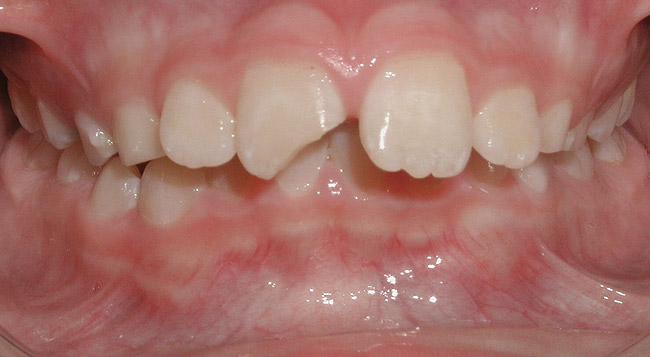

Although most orthodontic treatment begins between the ages of 9 and 14,1 a number of problems are most effectively treated at an earlier age, as delineated in Table 1. Although it is outside the scope of this article to discuss in detail each item listed, the case of excessive protrusion of upper incisors provides insight into the importance of referring patients to the orthodontist in a timely fashion. According to Proffit, there is an approximately 33% chance that a patient with excessive overjet will experience trauma to the upper incisors (Figure 2), thus a prompt referral is essential to greatly decrease the risk of potential trauma.2

Figure 2 A 10-year-old patient with excessive overjet who fractured a protruding maxillary incisor.

Figure 2